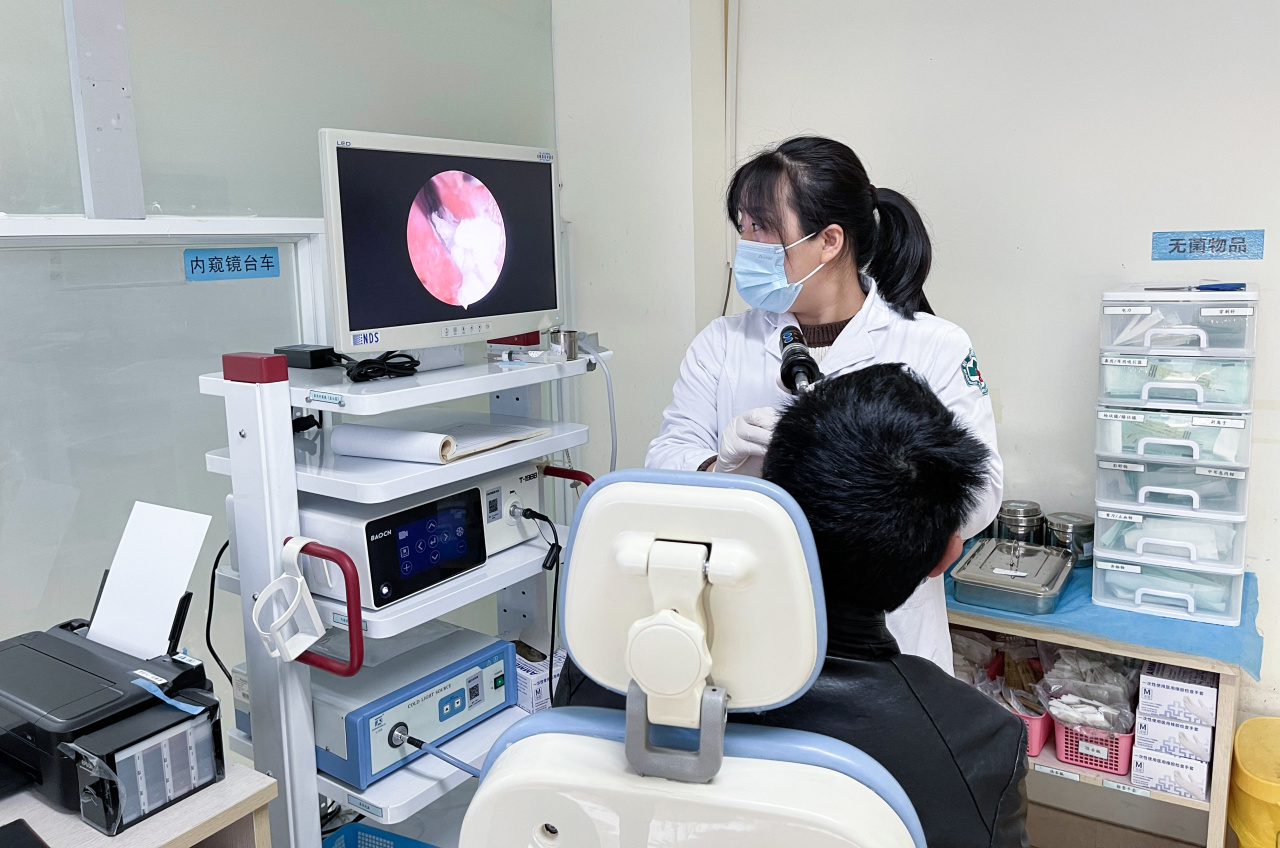

面对耳部健康的重重挑战,我院耳鼻喉科汇聚了一支医术精湛、经验丰富的团队。他们精通各类耳部疾病的诊断与治疗,从常见的外耳道炎、中耳炎,到复杂的突发性耳聋、梅尼埃病等疑难杂症,凭借专业知识与前沿技术精准施策。

科室配备了先进的听力检测设备,如纯音测听仪、声导抗仪等,能够全方位、高精度地评估耳部功能,精准捕捉听力细微变化,为疾病诊断提供可靠依据。在治疗手段上,我们紧跟医学前沿,开展了微创鼓室成形术治疗中耳炎,最大限度保留耳部结构与功能;针对突发性耳聋,采用个性化的综合治疗方案,争分夺秒挽救听力。